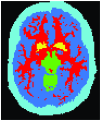

In this section, we review the prior knowledge information devised to improve image segmentation. Table 1 presents some of these important priors and compares them in terms of the nature of achievable solution due to a given formulation (i.e. globally vs. locally optimal), metrication error, domain of action (continuous vs. discrete), and other properties. We also created an interactive online database to categorize existing works based on the type of prior knowledge they use. We made our website interactive so that researchers can contribute to keep the database up to date. Figure 8 illustrates a snapshot of our online database showing different prior information that have been used in the literature for targeted image segmentation.